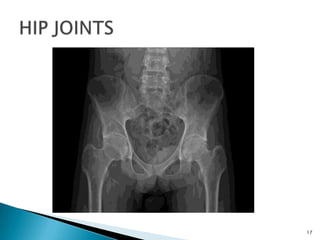

 RADIOLOGICAL